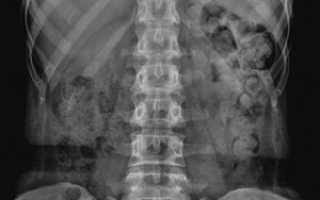

• также может понадобиться рентген органов брюшной полости;

imageЧаще всего проводят рентгенографию брюшной полости, с помощью которой выявляется наличие газов и высота стояния диафрагмы. Чтобы оценить количество газов применяют быстрое введение в кишечник аргона. При этом удается измерить объем вытесняемых аргоном кишечных газов. Кроме того, применяют следующие методы диагностики: